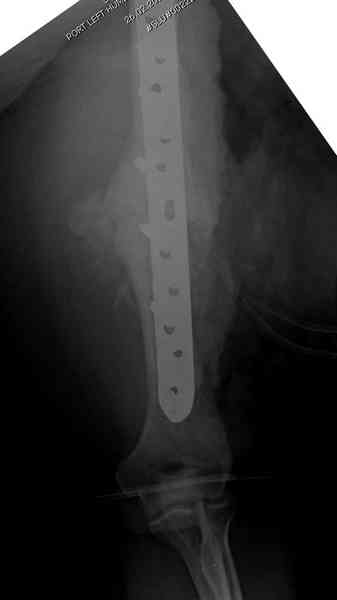

ложного сустава плеча могут быть различными, кто-то предпочитает аппаратом Илизарова (Соломин), пластинами (Волна) или интрамедуллярным гвоздем (Челноков).

Первичную пластину убрали недели 6 назад из переднего оригинального доступа, и из-за подозрительности тканей вокруг пластины, решили провести реконструкцию поэтапно.

имплантов для плеча, но для этого случая сделали

исключение. На снимке 4А диаметр мягких ткани около 20 см, при весе больной более 135 кг, и также выступление Андрея Волны подстегнуло к применению более массивной 4.5 мм локинг пластины.